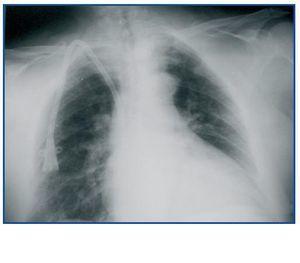

Es importante no confundir el abordaje a la vena innominada con el que se practica para la vena subclavia vía supraclavicular, este se lleva a cabo por punción inmediatamente por arriba de la clavícula, pero lateral externo al haz clavicular del esternocleidomastoideo (figura 1) y en dirección medial exigiendo la permeabilidad de la vena subclavia10,11.

Figura 1.